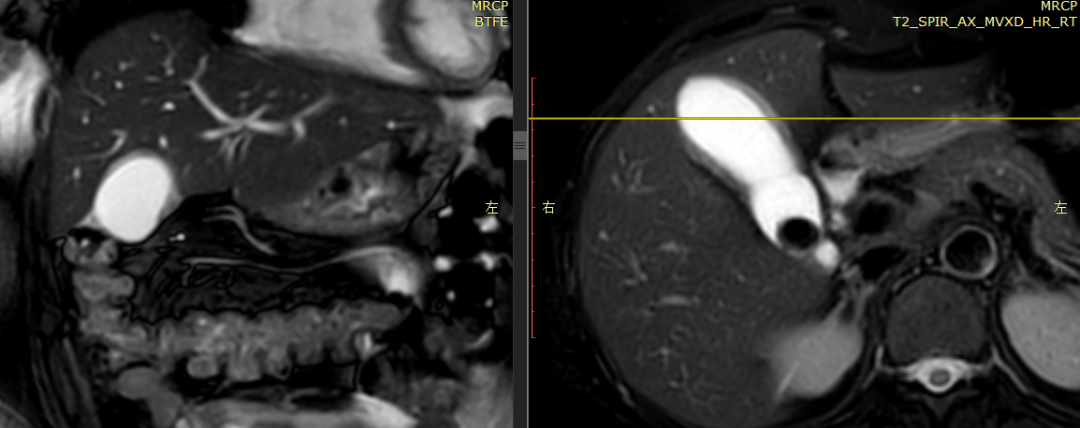

CASE 2